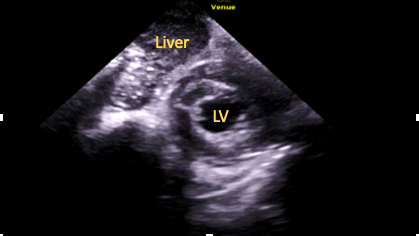

Subcostal Short-Axis Mid-Papillary Level

Further apical tilt will bring the papillary muscles into view, allowing for assessment of LV radial contraction (Figure 9).15

Figure 9. Subcostal short-axis mid-papillary muscle view.

RV=right ventricle, ALPM=anterolateral papillary muscle, PMPM=posteromedial papillary muscle

Subcostal Short-Axis Apical Level

Even further apical tilt will bring the LV apex into view (Figure 10), allowing for assessment of function and for the presence of thrombi.15

Figure 10. Subcostal

short-axis apical level view.

LV=left ventricle cavity